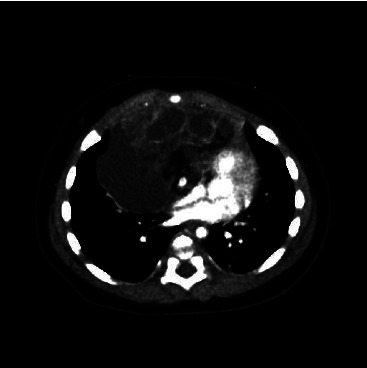

Tracheal intubation under sedation in uncooperative infants is challenging. The case of a 4-month-old infant with a massive anterior mediastinal tumor and upper respiratory tract symptoms, for whom effective preoxygenation was provided with a high-flow nasal cannula (HFNC), allowing for safe tracheal intubation in combination with a supraglottic device and local anesthetic, is reported. With careful planning of anesthesia and creative problem solving, airway management for anterior mediastinal tumors can be performed safely with the selection of an appropriate airway device. This may be a good airway management strategy for infants with mediastinal tumors or who may be expected to have ventilation difficulties.